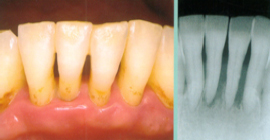

- 口腔内診査視診や歯周ポケット検査によって、虫歯の有無や歯周病の進行状態を診ます。

- レントゲン診査視診では見つけにくい深い所の虫歯や、骨の中の状態を診ます。

- スケーリング(歯石除去)超音波で汚れを浮かし・剥がす器具を使って、歯の汚れ(歯垢や歯石)を取り除き、清潔にします。

- PMTC(歯面研磨)『プロフェッショナル・メカニカル・トゥース・クリーニング』と言われるもので、専用のブラシと研磨剤を使って、着色してざらざらになった歯の表面を研磨して、歯垢の付きにくいつツルツルの歯にします。

毎日のブラッシングでは落としきれない歯垢や歯石などをしっかりと取り除き、歯を清潔な状態に保つことが大切です。